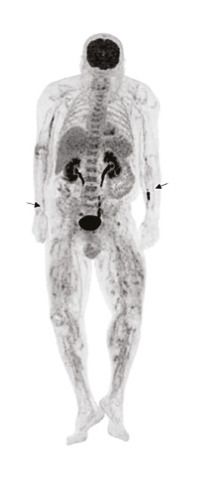

L’élimination des diagnostics différentiels est importante pour retenir le diagnostic de PAN. La fréquente altération de l’état général présente chez les patients doit conduire en premier lieu à rechercher une néoplasie solide, une hémopathie maligne ou une infection de type tuberculose, endocardite, etc.4 La réalisation d’une tomodensitométrie thoraco-abdomino-­pelvienne (TDM-TAP) avec temps artériel, permet de rechercher ces diagnostics différentiels mais peut aussi révéler les sténoses, occlusions et anévrismes des moyens vaisseaux. La tomographie par émission de positons au fluorodésoxyglucose (TEP-FDG) peut avoir le même rôle de recherche de ces diagnostics différentiels et peut révéler une hyperfixation des artères de moyen calibre, associée à une hyperfixation musculaire, fortement évocatrice de PAN (fig. 7).24 Les autres vascularites constituent aussi des diagnostics alternatifs. Notamment la présence d’ANCA ou d’une cryoglobulinémie à taux significatif a tendance à exclure le diagnostic de PAN.1,25